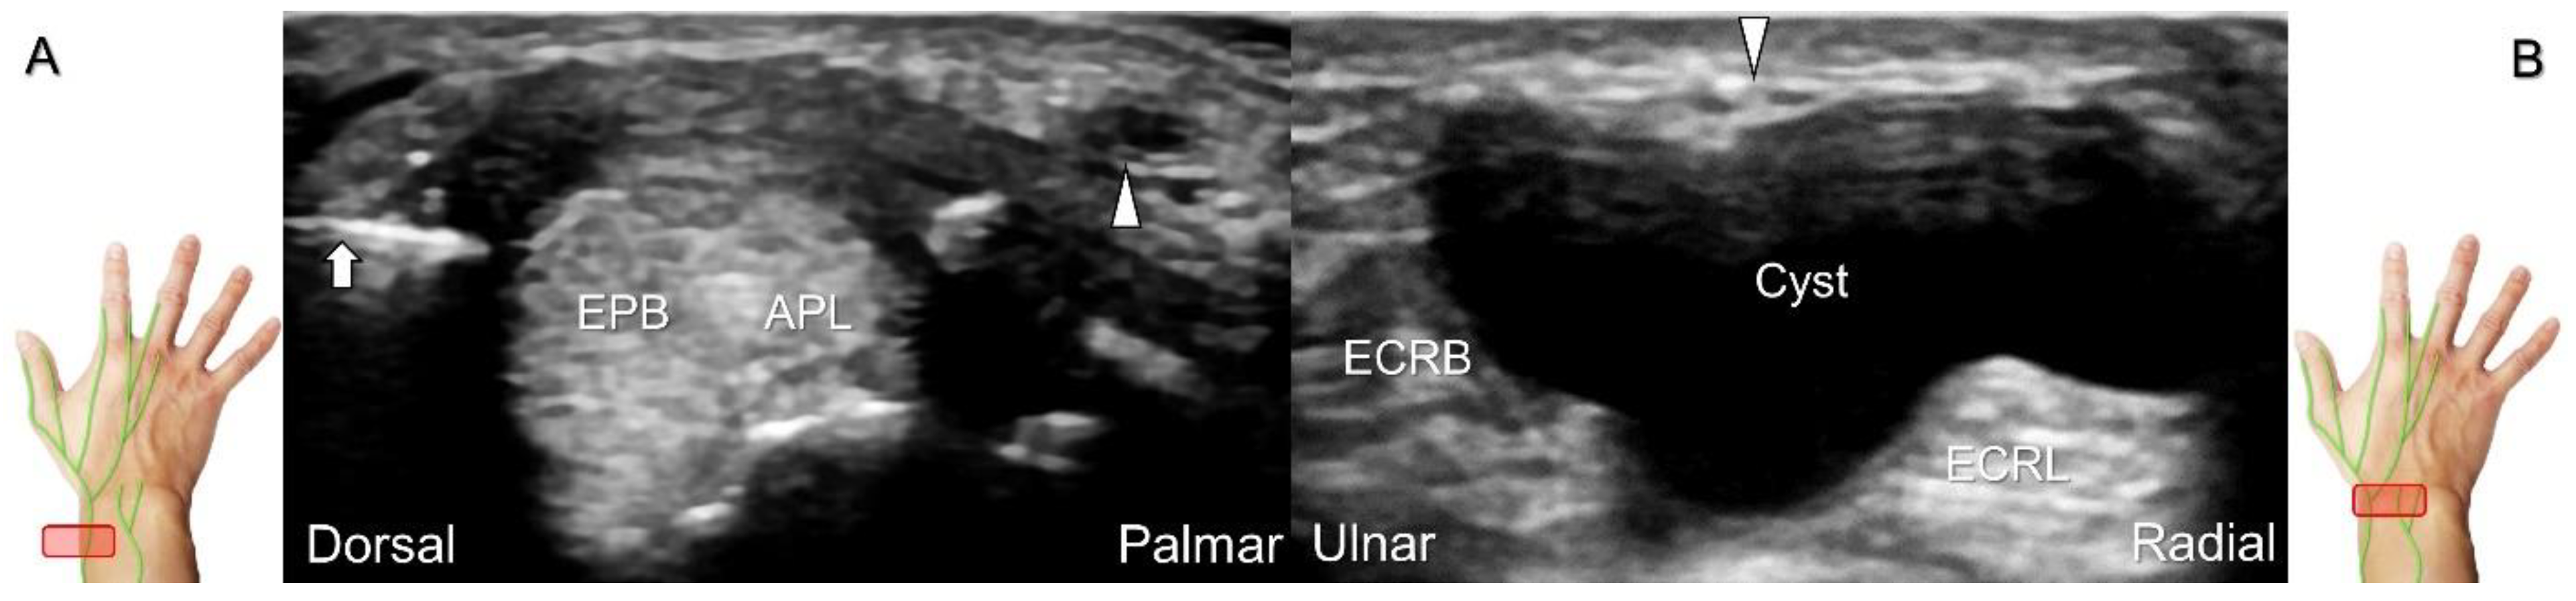

Additionally, acupuncture and cannulation of the cephalic vein over the distal forearm can lead to nerve injury. To prevent iatrogenic injury, the superficial radial nerve before injection should also be recognized for de Quervain’s syndrome (Figure 23A) [44], ganglion cyst aspiration (Figure 23B), and catheterization (Figure 24A–C). For injection of the superficial radial nerve, an in-plane approach in the nerve’s short axis is preferred (Figure 24D).

Figure 23. Sonographic imaging of the superficial radial nerve beside the first extensor compartment of the wrist (A), and a ganglion cyst over the second extensor compartment of the wrist (B). White arrowheads: superficial radial nerve; white arrow: needle. APL: abductor pollicis longus tendon; EPB: extensor pollicis brevis tendon; ECRL: extensor carpi radialis longus tendon; ECRB: extensor carpi radialis brevis tendon.